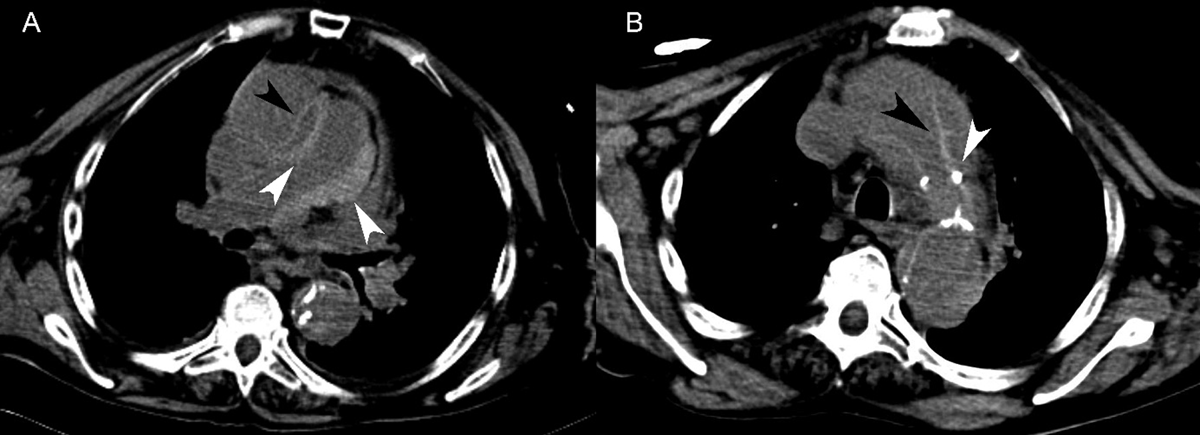

Figure 3

Patient 3. (A) Non-contrast-enhanced CT showed circumferential high attenuation along the walls of the main and right pulmonary arteries, consistent with pulmonary artery intramural hematoma (white arrowheads). Stanford type A aortic dissection with an intimal flap in the ascending aorta was also seen (black arrowhead). (B) Non-contrast-enhanced CT revealed an intimal flap of the thoracic aorta (black arrowhead) and displacement of atherosclerotic calcifications into the aortic lumen (white arrowhead).